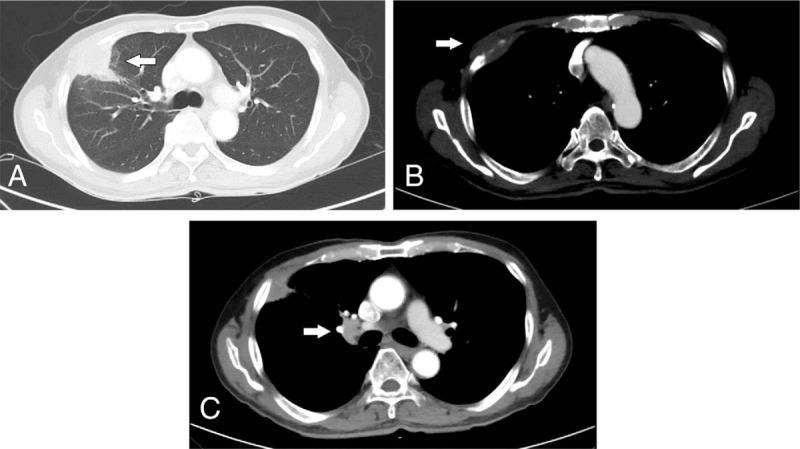

He has survived more than two years since his initial diagnosis, maintaining his good performance status. Serial imaging with computed tomography scans showed tumour regression and near-complete resolution of his disease.

自初次诊断以来,他已存活两年多,保持了良好的身体状况。计算机断层扫描的系列成像显示肿瘤消退且疾病几乎完全缓解。